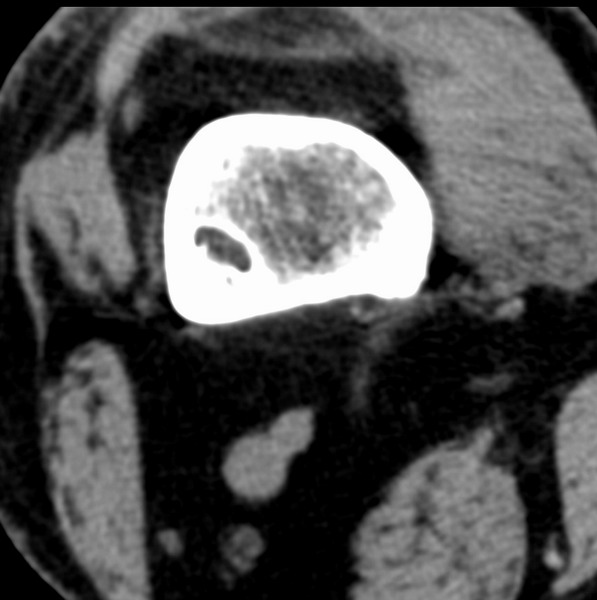

右侧膝关节疼痛一月

男、48

股骨下段、胫骨上段。

1、股骨干骺端病变考虑干骺端纤维性皮质缺损愈后(非骨化性纤维瘤)改变,胫骨近端内生骨瘤(或干骺端纤维性皮质缺损愈后改变);

2、骨关节炎,骨质增生,股骨外侧髁退变性囊肿(关节面软骨下囊肿);

股骨干骺端病变考虑干骺端纤维性皮质缺损愈后(非骨化性纤维瘤)改变,胫骨近端内生骨瘤(或干骺端纤维性皮质缺损愈后改变);

多发内生软骨瘤!

1、股骨干骺端病变考虑干骺端纤维性皮质缺损愈后(非骨化性纤维瘤)改变,胫骨近端内生骨瘤;

股骨干骺端病变考虑非骨化性纤维瘤。

支持非骨化性纤维瘤

非骨化性纤维瘤